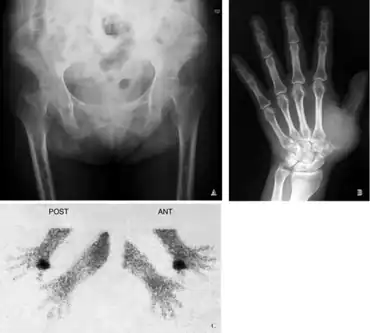

Radiographic characteristics

Radiological appearances include:

- Pseudofractures, also called Looser's zones.

- Protrusio acetabuli, a hip joint disorder

Additional imaging

In certain types of osteomalacia the following imaging techniques may be used:[18]

Furthermore, a technetium bone scan will show increased activity (also due to increased osteoblasts).